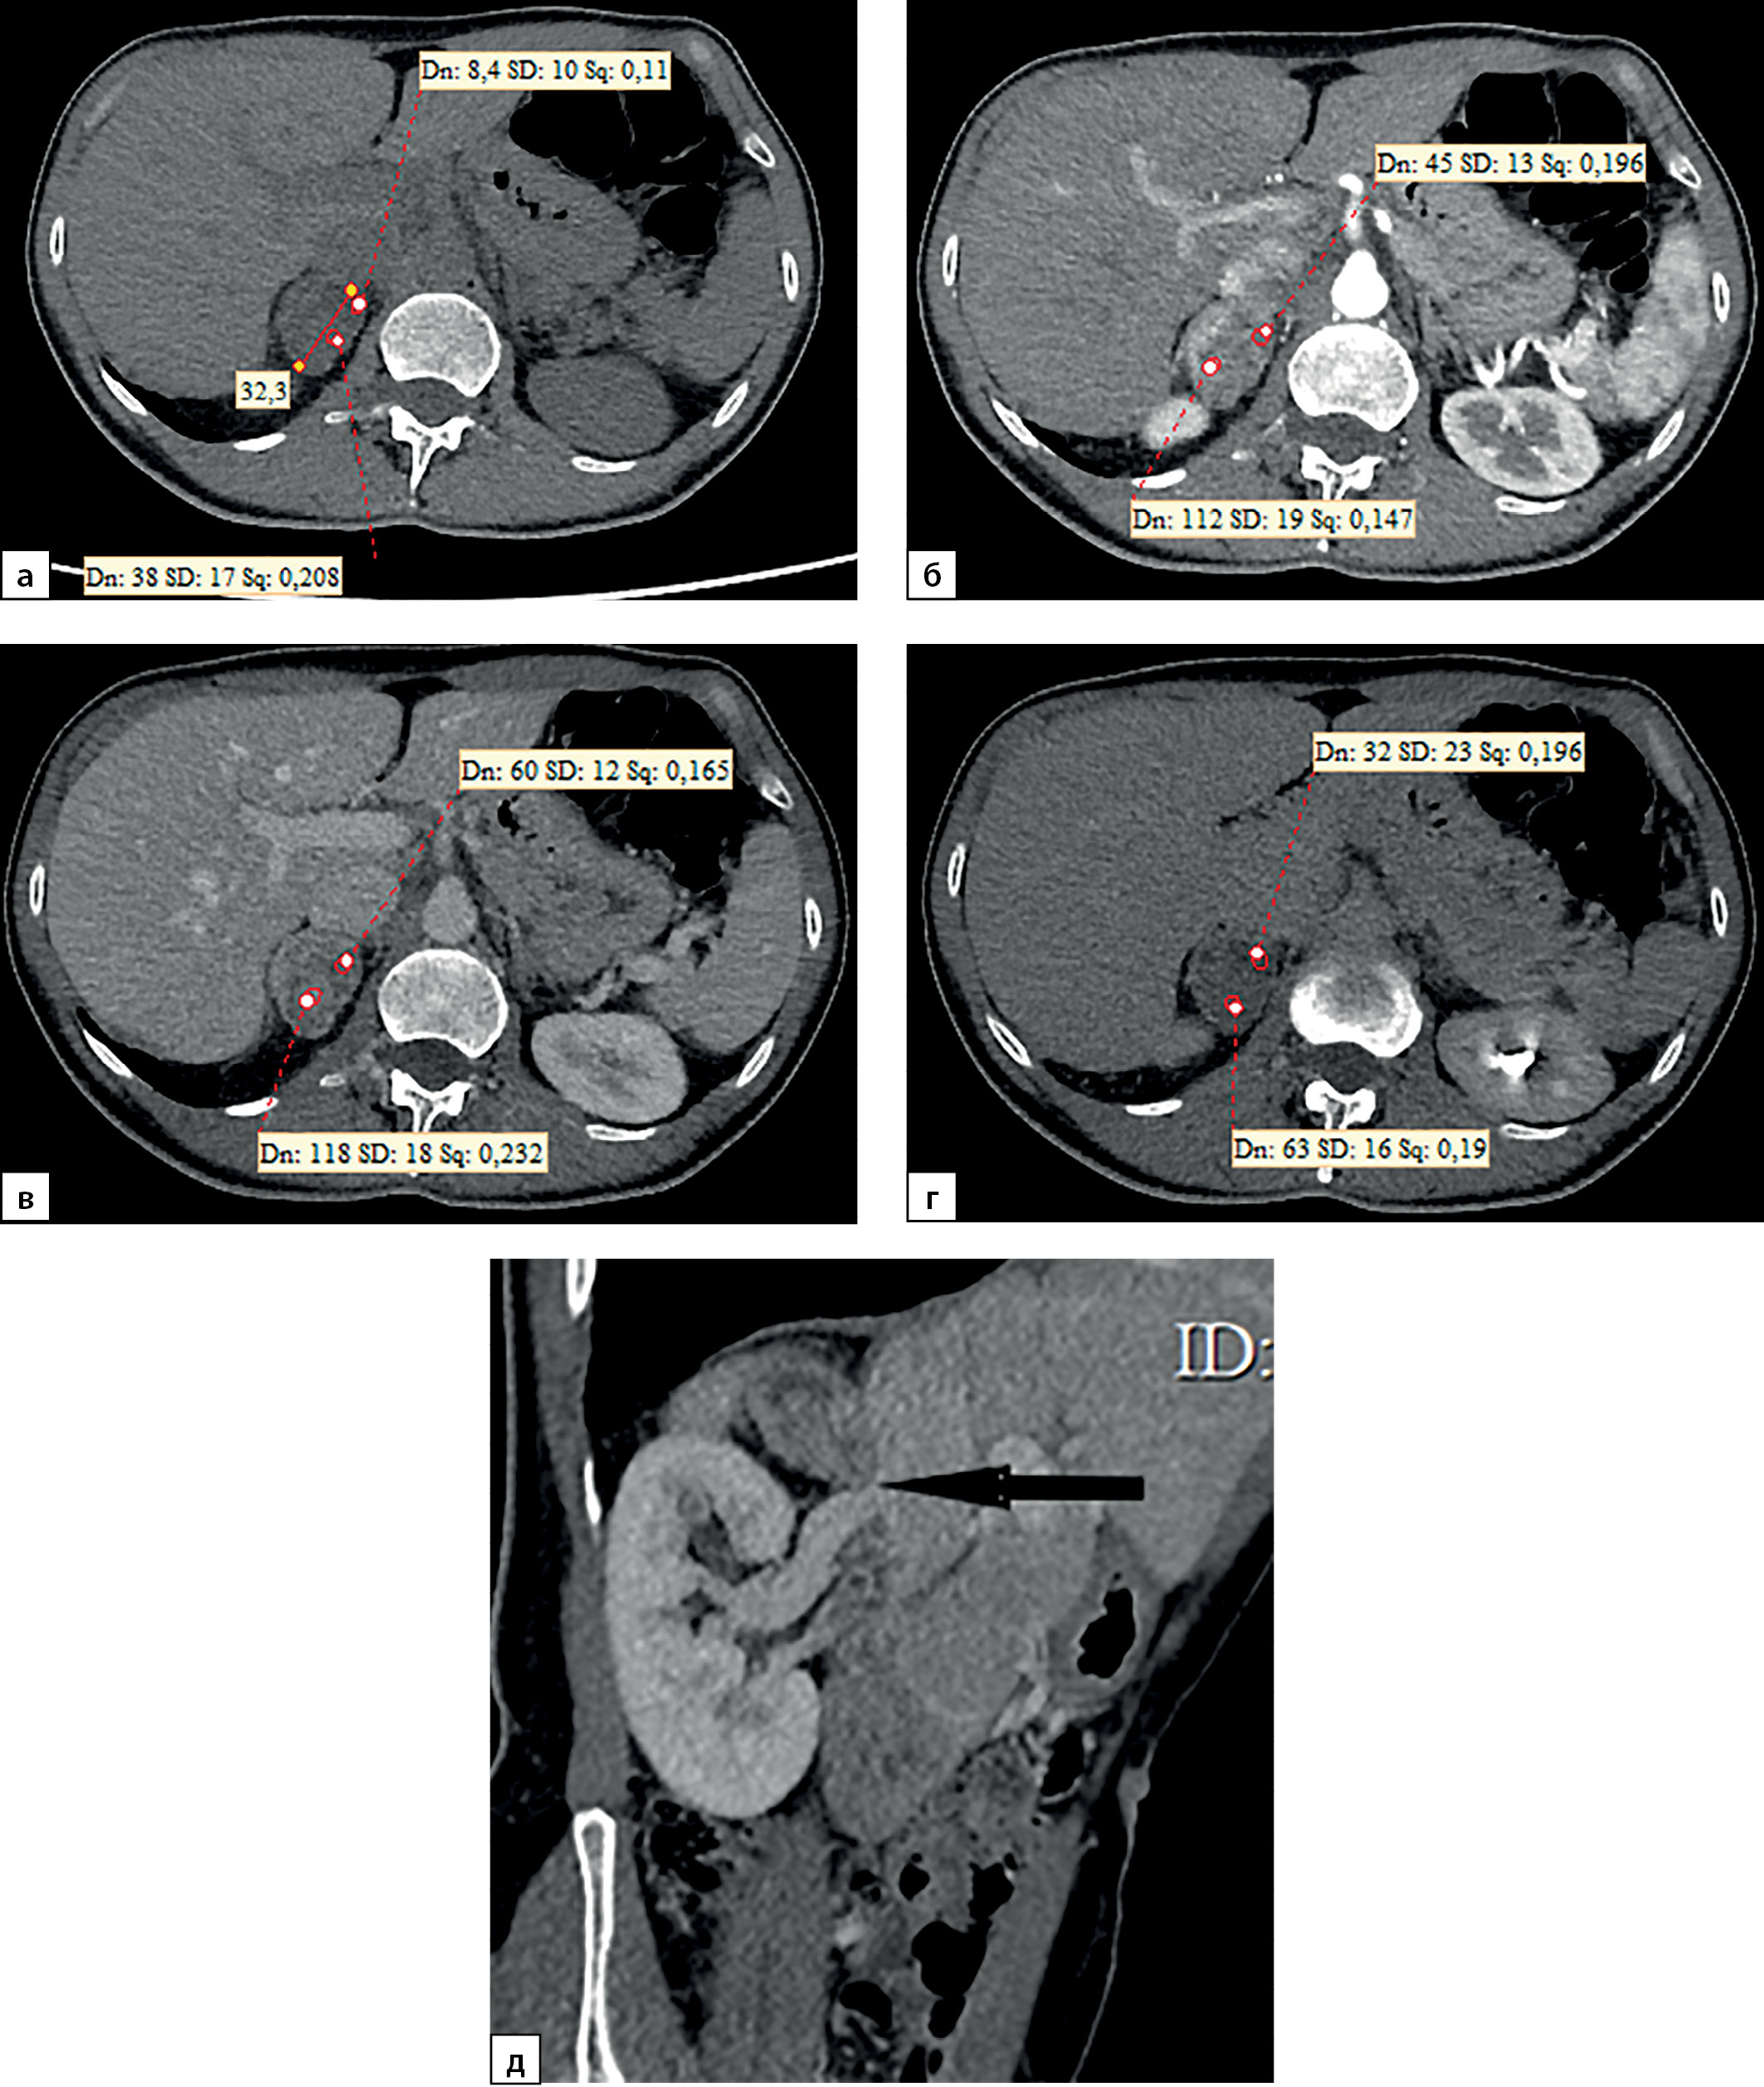

Медиана и интерквартильный размах максимальной нативной плотности АКР составили 32,0 (28,0–31,5) HU. Показатели нативной плотности в интервале от +10 до +30 HU отмечены у 22 больных (31,4%) пациентов, от +30 до +40 HU у 37 (52,9%) человек и свыше +40 HU в 10 (14,3%) наблюдений. Необходимо отметить, что в анализируемых наблюдениях встретился 1 пациент и с меньшей чем +10 HU нативной плотностью опухоли (рис. 9, 10). При выполнении денситометрии сознательно избегали попадания в зону измерения участков некроза, кистозных включений и кальцинатов.

Рисунок 9. Компьютерные томограммы пациентки С., 44 лет с крупной опухолью правого надпочечника размерами (66 мм): а — изображение в аксиальной плоскости, нативная фаза сканирования; образование имеет четкие ровными контуры, умеренно диффузно неоднородную структуру с низкими денситометрическими показателями от +2,2 до +7,2 HU; б — артериальная фаза постконтрастного сканирования; в — венозная фаза; г — фаза отсроченного сканирования. Коэффициент абсолютного вымывания контрастного препарата составил 42%, относительного — 38,1%.

Figure 9. Computed tomography of patient S., 44 years old, with a large tumor of the right adrenal gland (66 mm): a — image in the axial plane, native scanning phase; the formation has clear, even contours, a moderately diffusely heterogeneous structure with low densitometric values from +2.2 to +7.2 HU; b — arterial phase of post-contrast scanning; c — venous phase; d — delayed scan phase. The coefficient of absolute washout of the contrast agent was 42%, relative — 38.1%.